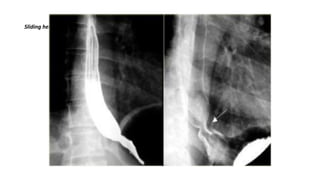

• Barium meal in Trendlenberg position. Displacement of the cardio-esophageal junction above the

esophageal hiatus . Part of the stomach is present in the chest

• Reflux of barium into the esophagus

Sliding hernia

Air-contrast esophagram showsthick esophageal mucosal folds (arrows) and an ulcer (arrowhead) due to GERD. Single contrast esophagram shows stricture (arrow) and sliding hiatus hernia